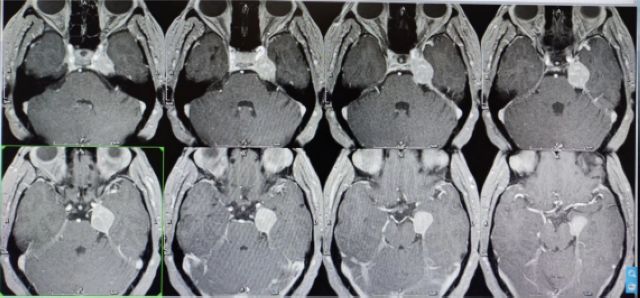

伽玛刀治疗前

伽玛刀治疗后

近期,徐女士来院复查

颅内肿瘤明显减小

治疗效果极佳